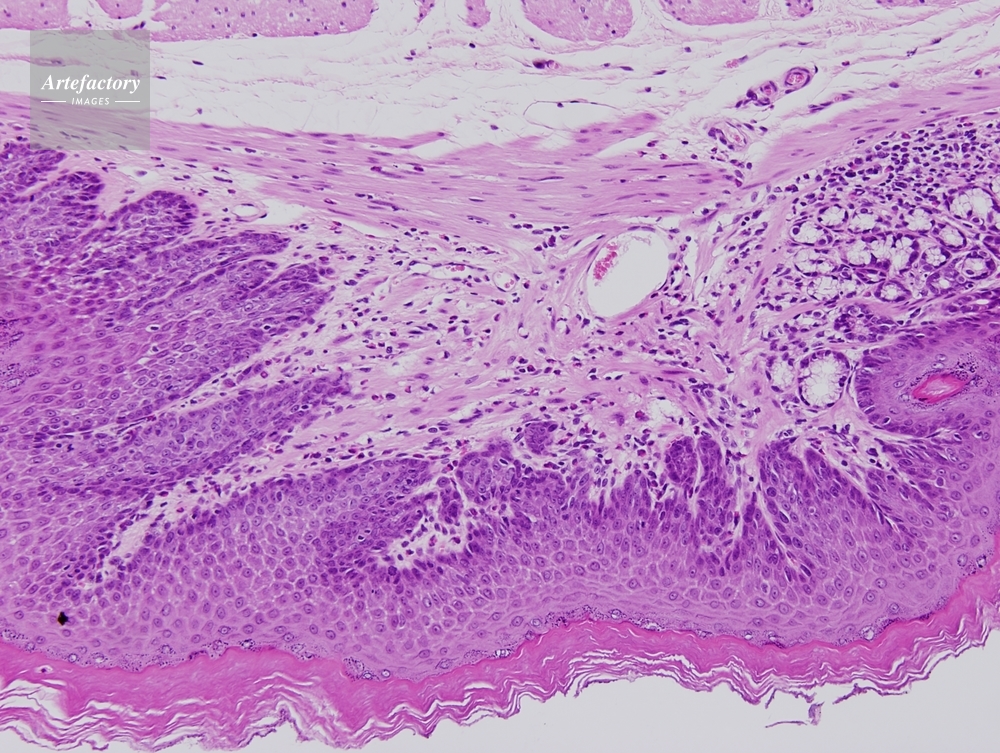

| 作品タイトル | ヒト 膀胱(urinary bladder) | モデルリリース | なし | |